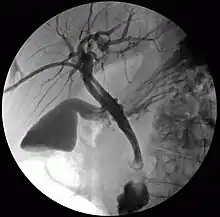

Colangiografia percutânea transhepática (CPT) ou colangiografia percutânea trans-hepática é uma técnica radiológica usada para visualizar a anatomia do trato biliar. Um meio de contraste é injetado em um ducto biliar no fígado, após o qual os raios X são feitos. Permite o acesso à árvore biliar nos casos em que a colangiopancreatografia retrógrada endoscópica (CPRE) não tem êxito. Relatado inicialmente em 1937, o procedimento se tornou popular em 1952.[1][2]